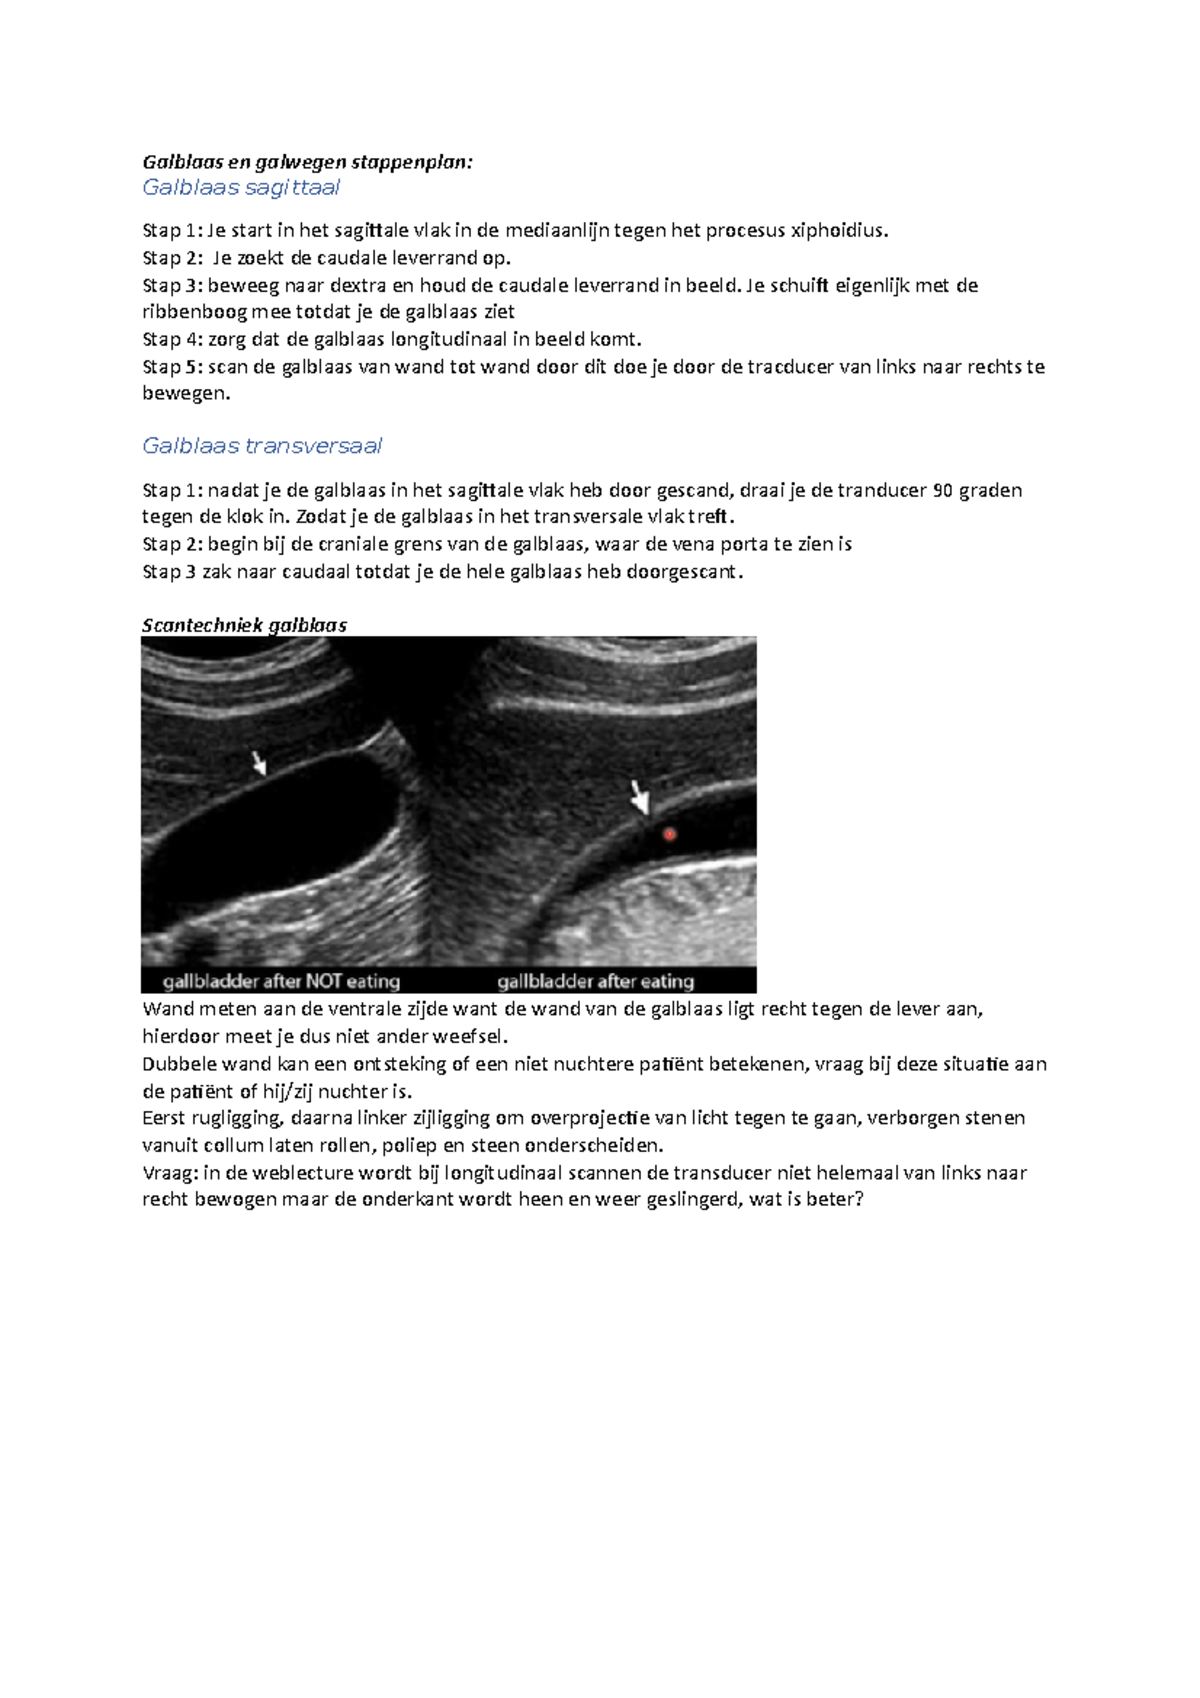

Stappenplan EC galblaas en galwegen Galblaas en galwegen stappenplan Galblaas sagittaal Stap